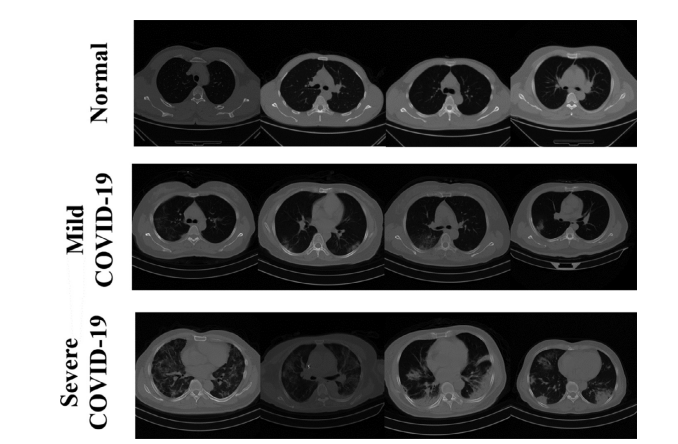

Fig. 1. Partial sample of the dataset.

图1. 数据集的部分样本。